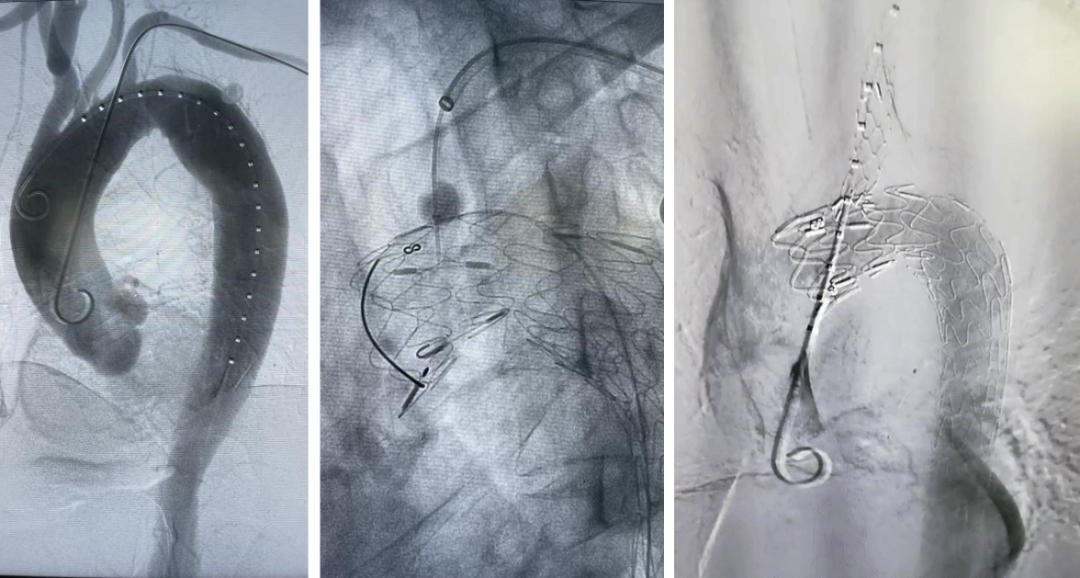

(术前3D模型显示,患者为B型主动脉夹层,弓上有4个分支动脉,且左锁骨下动脉与迷走左椎间距8mm,破口长度约30mm,手术对支架定位要求高。)

(术中主体支架成功锚定在迷走左椎开口后沿,原位破膜成功,并成功封堵大破口,主体、分支和迷走左椎均显影良好。)